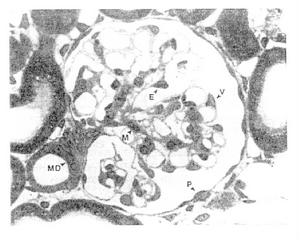

發病機制: 腎小球疾病的病因還未完全闡明,它們發病機理也不盡相同但可以認為免疫因素是它們致病的主要機制。

其它輔助檢查: 腎穿刺活組織檢查:該檢查可以為確定腎病綜合徵和病理類型提供形態學診斷並對治療方案確定的及估計預後有著指導性意義。